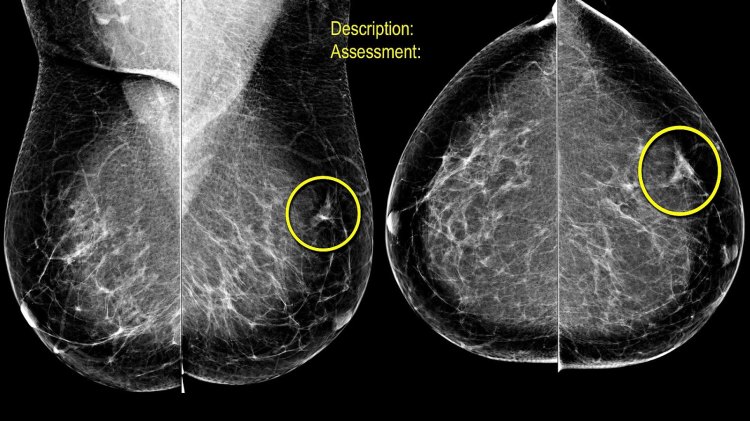

La mastografía es un estudio de imagen utilizado para la detección temprana de enfermedades mamarias, en especial el cáncer de mama. Este procedimiento radiológico permite identificar anomalías en el tejido mamario, incluso antes de que sean palpables. Conocer cómo se lleva a cabo y la duración del examen es fundamental para aquellas personas que desean realizarse la prueba y obtener un diagnóstico oportuno.

mastographyLa mastografía se realiza en un equipo especializado denominado mamógrafo. Este dispositivo utiliza dosis bajas de radiación para obtener imágenes detalladas de la estructura interna de las mamas. El procedimiento sigue una serie de pasos específicos:

4. Captura de imágenes: Se toman al menos dos imágenes de cada mama en diferentes ángulos. En algunos casos, el especialista puede solicitar proyecciones adicionales para una evaluación más detallada.